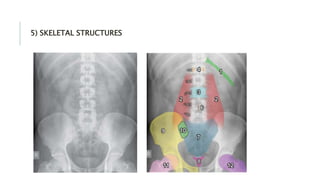

5) SKELETAL STRUCTURES